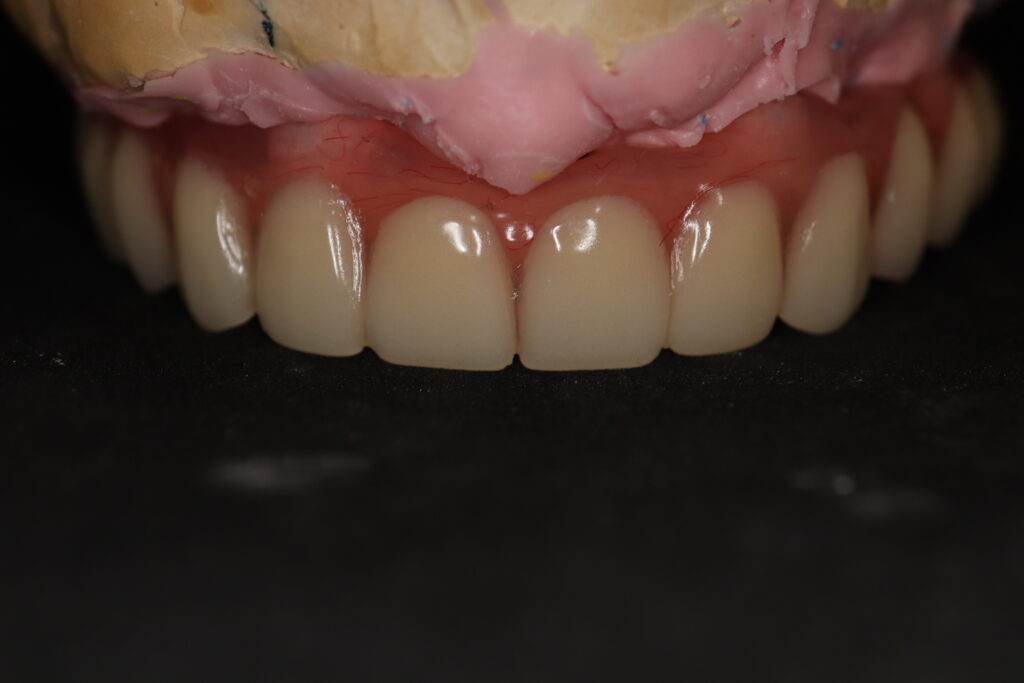

Процесс работы

После установки 6ти имплантантов Megagen Anyone, было принято решение зафиксировать металлоакриловый протез протез на 4 имплантата.

2 крайних имплантата, установленных в бугры, были ушиты с целью дальнейшего приживления. При постоянном протезирование протез будет зафиксирован на 6ти имплантатах.

Спустя 7 дней на верхней челюсти зафиксирован металлоакриловый протез из 12 зубов с опорой на 4 дентальные имплантата.

протез